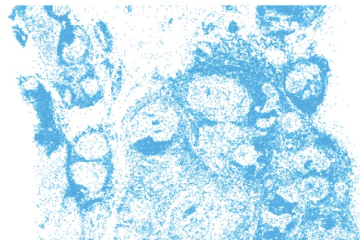

Samen spelen voor kankeronderzoek, dat is waar de game Tilly over gaat. Het is een uitdagende puzzelgame over onze cellen. Het doel is Tilly voeden door alle cellen weg te spelen. Wat is een tumorcel, wat is een immuuncel? Daar wordt Tilly blij van. Tilly is namelijk een algoritme en het heeft als doel om voor zoveel mogelijk patiënten immuuntherapie beschikbaar te maken, te beginnen voor patiënten met borstkanker. Voorwaarde is dat Tilly nog slimmer wordt en hiervoor heeft het veel kennis van cellen nodig. Data die nu ontbreken. Wij kunnen spelenderwijs Tilly voeden. Met elke cel die we in kaart brengen, maken we Tilly intelligenter. Kortom, elke cel telt.

Door deze game te spelen geven we onderzoekers de data om Tilly te trainen. Elke cel telt en zo leveren we samen een belangrijke bijdrage aan het onderzoek naar immuuntherapie. In totaal hebben spelers met de game nu bijna 400.000 annotaties opgehaald, verdeeld over de 3 celtypen. Genoeg data voor het wetenschappelijke team om een algoritme mee te trainen. Met een nauwkeurigheid van 82% scoort dit algoritme nagenoeg net zo goed als dat van de expert, 83%. De conclusie is daarom dat samen spelen niet alleen loont, het levert onmisbare brandstof voor het trainen van algoritmes. Iedere groei aan spelers betekent een veelvoud aan data die eerder niet voorhanden was. Het volgende doel is daarom om 1 miljoen annotaties te verzamelen om te onderzoeken in hoeverre we hiermee samen de nauwkeurigheid van algoritme verder verhogen. Speel je mee?